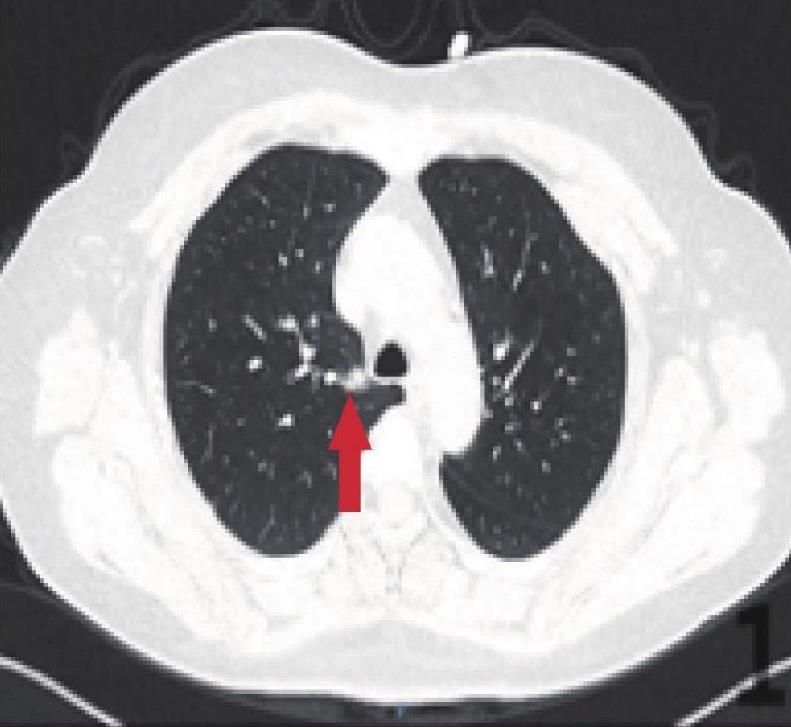

a.右肺部分实性结节

b.抗感染治疗后完全吸收